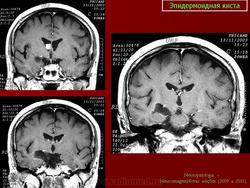

Эпидермоидная киста

Эпидермоидная киста.